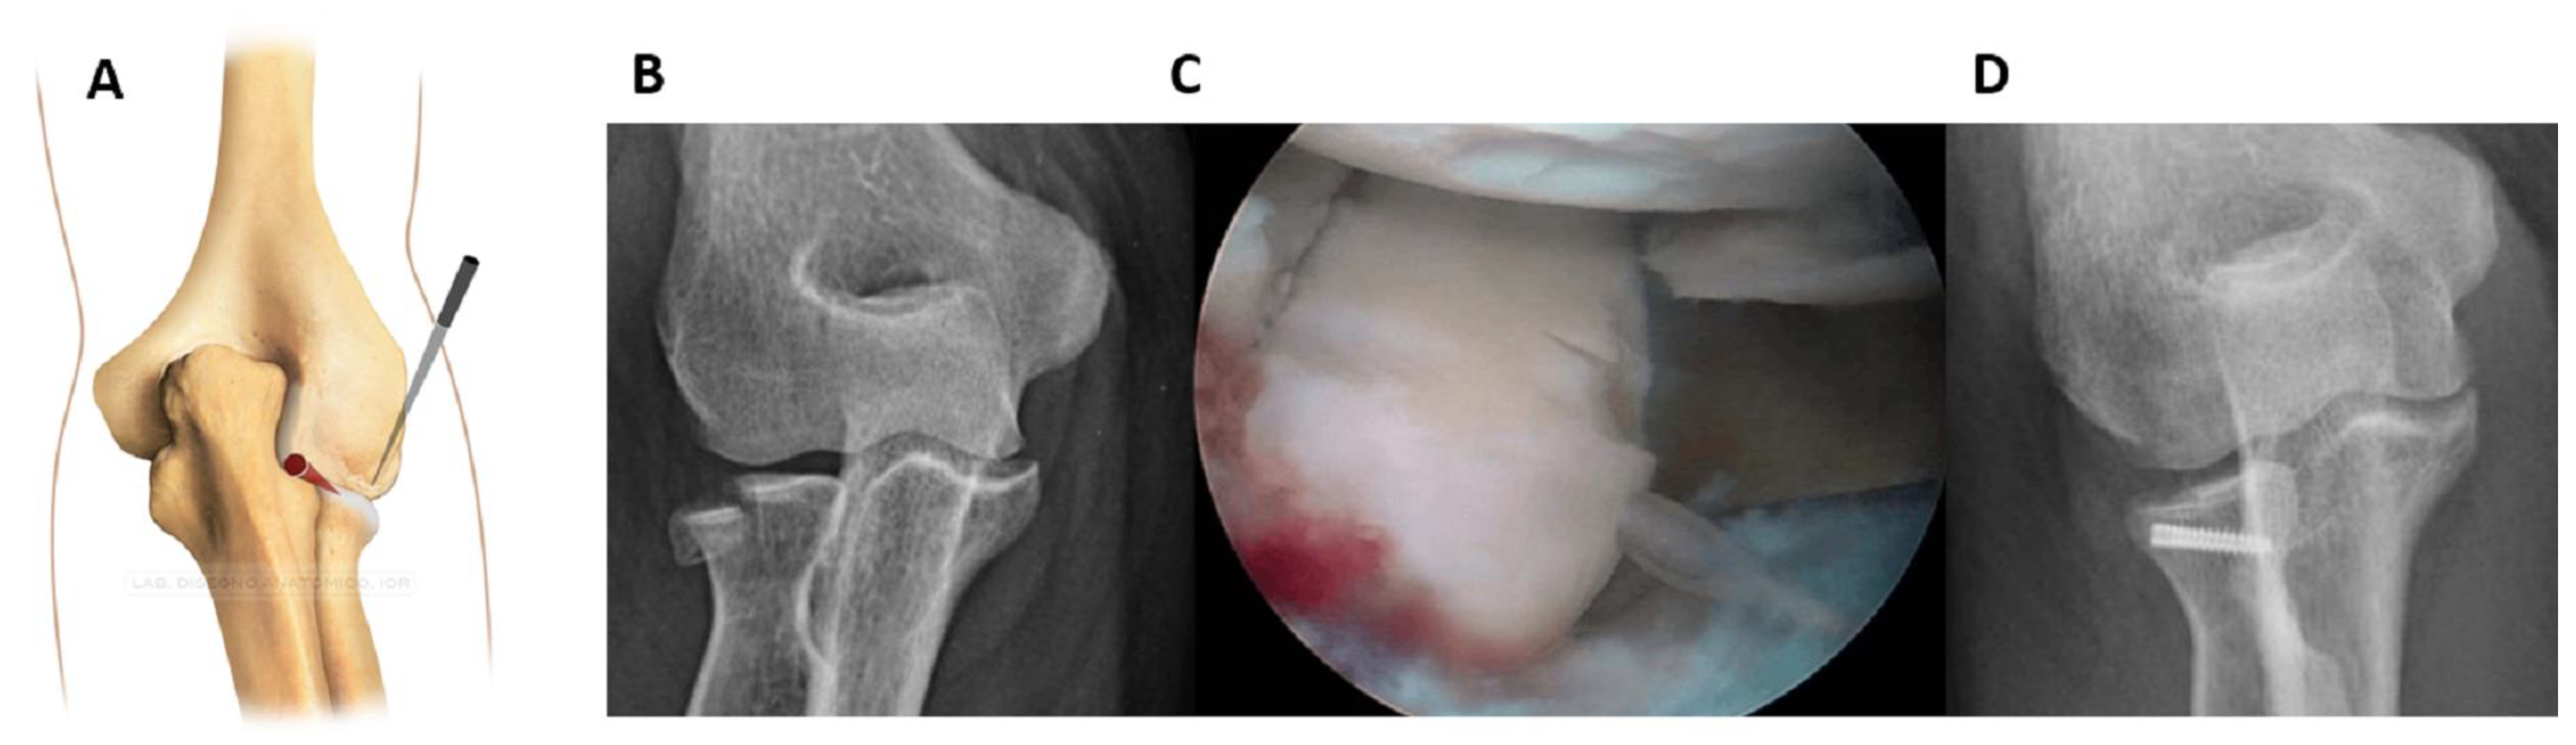

For medial half fractures, it was helpful to change the view (working position AM, Figure 3).

While viewing from the anterolateral portal, the cannula was inserted through the anteromedial portal. The procedure for the fixation was the same, and no other accessory portals were needed.

Figure 3. For the medial half fractures, the working position AM was more appropriate; the field was viewed from the anterolateral portal and the cannula was inserted through the anteromedial portal (A). (B): Pre-operative 3D CT scan showing the fracture. (C): Intraoperative image of fracture fixation. (D): Control x-ray.